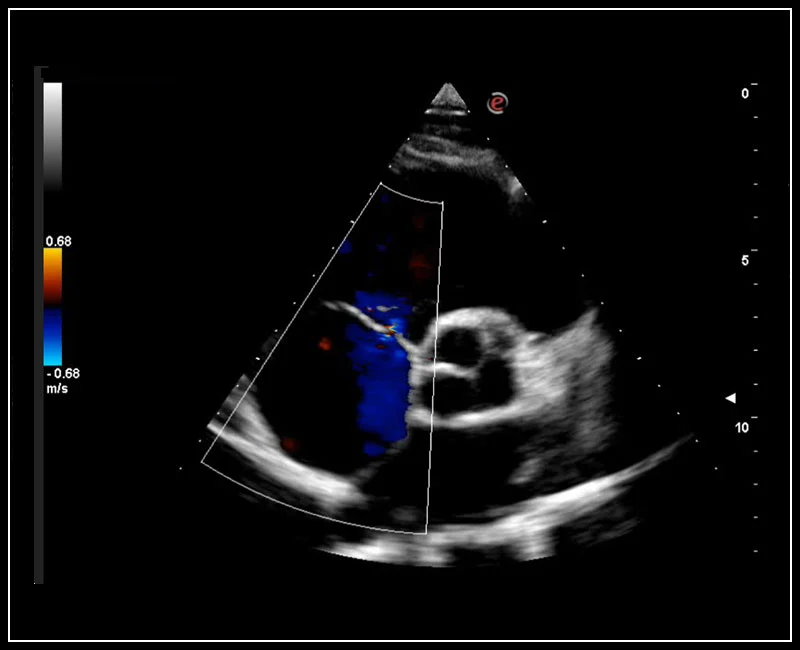

Q7 - Cardio CFM

Q7 - Cardio CFM